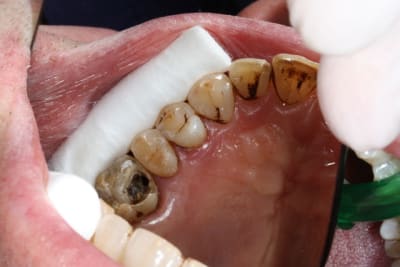

Voici le résultat d'une 3ème séance de recherche du MV 2 le vague à l'âme expliquant l'absence de digue , et mv 2 que j'aurai nommé le CCE pour casse couille endodontique mais n'étant pas endo exclusif je reste courtois avec cette désespérance souvent absente radiologiquement après obturation et dont le trajet incertain me laisse rêveur , quand à la guérison de l'image en mésial prions pour que Saint NaOCl et Saint EDTA veillent sur nous .

Et la paro partout, c'est à cause des tiges d'argent ?

Je salue ta conscience professionnelle, voire l'acharnement, je n'aurais probablement pas eu le courage d'une 3ème séance pour le mv2. D'ailleurs, je trouve que pour les reprises le mv2 me donne très souvent envie d'hurler, malgré l'attirail digue/loupes qui va bien. Sur des endos 1ère intention, je me sens plus attirée par ce foutu canal.